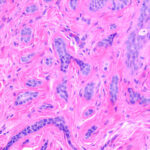

Histopathologic examination reveals a relatively well-circumscribed lesion in the upper two-thirds of the dermis with a focal epidermal connection. It is composed of basaloid aggregations arranged predominantly in columns and cords and admixed with infundibulocystic structures, surrounded by a dense, hypocellular desmoplastic stroma. It may occasionally be difficult to distinguish this entity histologically from malignant desmoplastic lesions such as aggressive growth basal cell carcinoma or MAC. Treatment. Local surgical excision is the preferred treatment